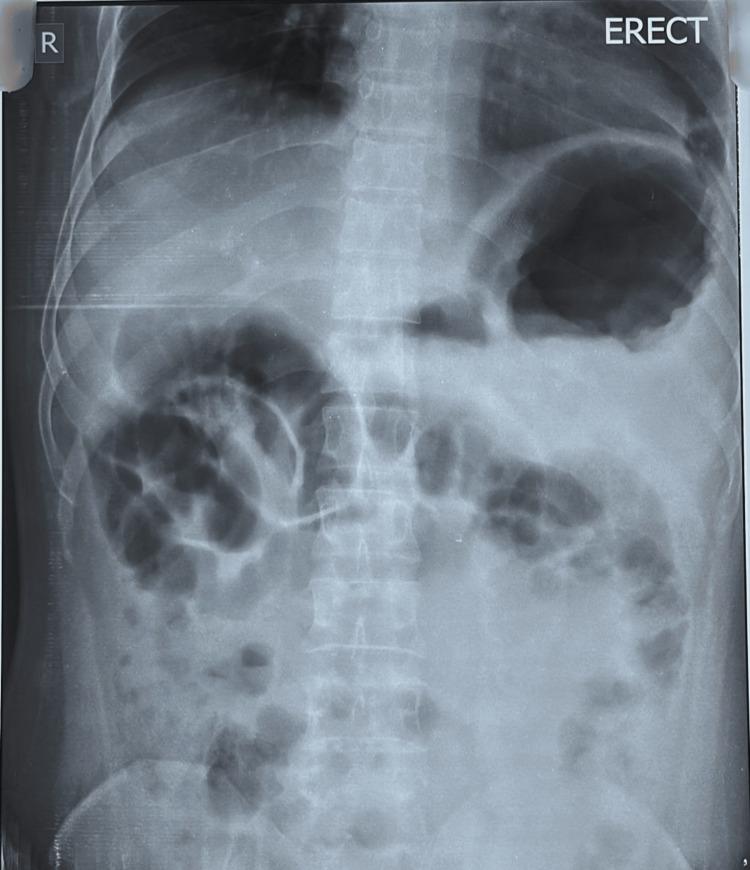

A contracted or "vanishing" gallbladder is a condition characterized by severe atrophy or fibrosis of the gallbladder, often resulting from chronic inflammation, recurrent cholecystitis, gallstone disease, or metabolic disorders such as diabetes and chronic alcohol use. The etiopathogenesis involves progressive fibrosis due to persistent biliary obstruction, chronic infection, or impaired blood flow, particularly in patients with liver cirrhosis. While the exact incidence remains unclear, it is more prevalent in individuals with long-standing hepatobiliary diseases or metabolic syndromes. Common symptoms include severe right upper quadrant pain, jaundice, nausea, vomiting, and signs of obstructive jaundice, such as dark urine and pale stools. Diagnostic investigations typically involve ultrasound, contrast-enhanced computed tomography (CECT), magnetic resonance cholangiopancreatography (MRCP), and endoscopic retrograde cholangiopancreatography (ERCP) to assess biliary obstruction, liver pathology, and gallbladder morphology. Treatment requires a multidisciplinary approach, including initial ERCP for biliary decompression, followed by surgical intervention (laparoscopic or open cholecystectomy), with conversion to open surgery often necessary due to dense adhesions and fibrosis. Postoperative care focuses on managing comorbidities, preventing complications, and long-term monitoring of liver health. This case report presents the challenging management of a 34-year-old male with a history of diabetes mellitus, chronic alcohol use, and liver cirrhosis, who presented with severe right upper quadrant pain, jaundice, and ascites. Initial evaluation revealed cholangitis, calculous cholecystitis with choledocholithiasis, and imaging findings consistent with liver cirrhosis. The patient underwent ERCP for biliary stenting and sludge extraction, followed by an attempted laparoscopic cholecystectomy. Intraoperatively, dense adhesions and fibrosis obscured the gallbladder, confirming a contracted or "vanishing" gallbladder, prompting conversion to an open procedure. The case highlights the diagnostic complexities of contracted gallbladders, which often result from chronic inflammation, fibrosis, or metabolic disorders. Preoperative imaging, including ultrasound and MRCP, played a critical role in identifying biliary obstruction and liver pathology. However, intraoperative findings necessitated adaptive surgical decision-making to mitigate risks such as bile duct injury or hemorrhage. The patient's multiple comorbidities further complicated management, emphasizing the need for a multidisciplinary approach involving gastroenterologists, surgeons, and hepatologists. Postoperative recovery was closely monitored for complications, including infection and bile leaks. The patient was discharged with follow-up care focusing on liver health, diabetes management, and alcohol cessation. This report underscores the importance of thorough preoperative assessment, flexibility in surgical technique, and collaborative care in optimizing outcomes for patients with complex gallbladder pathology. Future research should explore long-term outcomes and improved imaging techniques to enhance surgical planning for such challenging cases.

胆囊萎缩或“消失”是一种以胆囊严重萎缩或纤维化为特征的病症,通常由慢性炎症、复发性胆囊炎、胆结石病或代谢紊乱(如糖尿病和长期酗酒)引起。其发病机制涉及由于持续性胆管梗阻、慢性感染或血流受损导致的进行性纤维化,在肝硬化患者中尤为常见。虽然确切发病率尚不清楚,但在患有长期肝胆疾病或代谢综合征的个体中更为普遍。常见症状包括右上腹剧痛、黄疸、恶心、呕吐以及梗阻性黄疸的体征,如尿色深和大便色浅。诊断性检查通常包括超声、增强计算机断层扫描(CECT)、磁共振胆胰管造影(MRCP)和内镜逆行胆胰管造影(ERCP),以评估胆管梗阻、肝脏病理和胆囊形态。治疗需要多学科方法,包括首先进行ERCP以解除胆管梗阻,随后进行手术干预(腹腔镜或开腹胆囊切除术),由于致密粘连和纤维化,通常需要转为开腹手术。术后护理重点在于管理合并症、预防并发症以及对肝脏健康进行长期监测。本病例报告介绍了一名34岁男性患者的具有挑战性的治疗过程,该患者有糖尿病、长期酗酒和肝硬化病史,出现右上腹剧痛、黄疸和腹水。初步评估显示胆管炎、结石性胆囊炎伴胆总管结石,影像学检查结果与肝硬化相符。患者接受了ERCP胆管支架置入和胆泥清除,随后尝试进行腹腔镜胆囊切除术。术中,致密粘连和纤维化使胆囊难以辨认,证实为萎缩或“消失”的胆囊,促使手术转为开腹手术。该病例突出了萎缩性胆囊的诊断复杂性,这通常由慢性炎症、纤维化或代谢紊乱引起。术前影像学检查,包括超声和MRCP,在识别胆管梗阻和肝脏病理方面发挥了关键作用。然而,术中发现需要灵活的手术决策以降低胆管损伤或出血等风险。患者的多种合并症使治疗更加复杂,强调了需要胃肠病学家、外科医生和肝病学家参与的多学科方法。术后密切监测恢复情况以预防并发症,包括感染和胆漏。患者出院时接受以肝脏健康、糖尿病管理和戒酒为重点的随访护理。本报告强调了全面术前评估、手术技术灵活性以及协作护理对于优化复杂胆囊病理患者治疗效果的重要性。未来研究应探索长期预后以及改进成像技术,以加强对此类具有挑战性病例的手术规划。